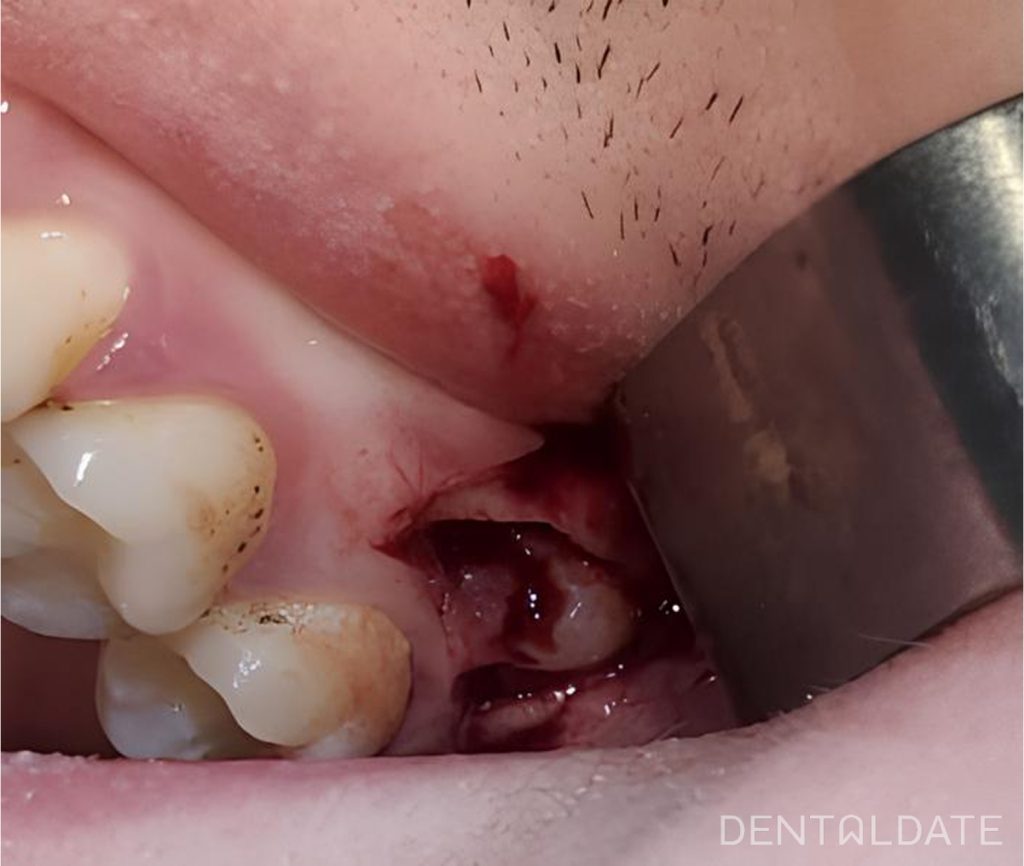

The incision was made in the retromolar area and in the area of tooth 27 3 mm above the gingival margin to prevent subsequent gingival recession in the area of the distal margin and distal papilla in the area of tooth 27. A part of the cortical bone was removed with a milling cutter and tooth 28 was divided into parts. Two extra-complete teeth were also extracted. Prolene 5\0 sutures.

Anti-inflammatory and desensitizing therapy was prescribed.